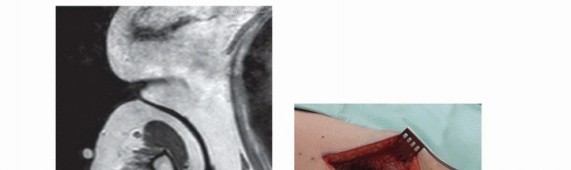

- التصوير بالرنين المغناطيسي (MRI): يوفر صورًا مفصلة للغاية للأنسجة الرخوة والعظام، مما يساعد في تحديد حجم الورم وامتداده وعلاقته بالهياكل المحيطة (الأوعية الدموية، الأعصاب).

- تعتبر الخزعة هي الطريقة الوحيدة المؤكدة لتشخيص نوع الورم (حميد أم خبيث) وتحديد نوعه الفرعي. يجب أن تتم الخزعة بواسطة جراح أورام عظام ذي خبرة مثل الأستاذ الدكتور محمد هطيف، حيث أن الخزعة غير الصحيحة قد تؤثر سلبًا على خطة العلاج المستقبلية.

يضمن الأستاذ الدكتور محمد هطيف أن كل خطوة في عملية التشخيص تتم بأقصى درجات الدقة والاحترافية، باستخدام أحدث التقنيات لضمان التوصل إلى تشخيص واضح ومحدد، والذي يشكل الأساس لخطة علاجية ناجحة.